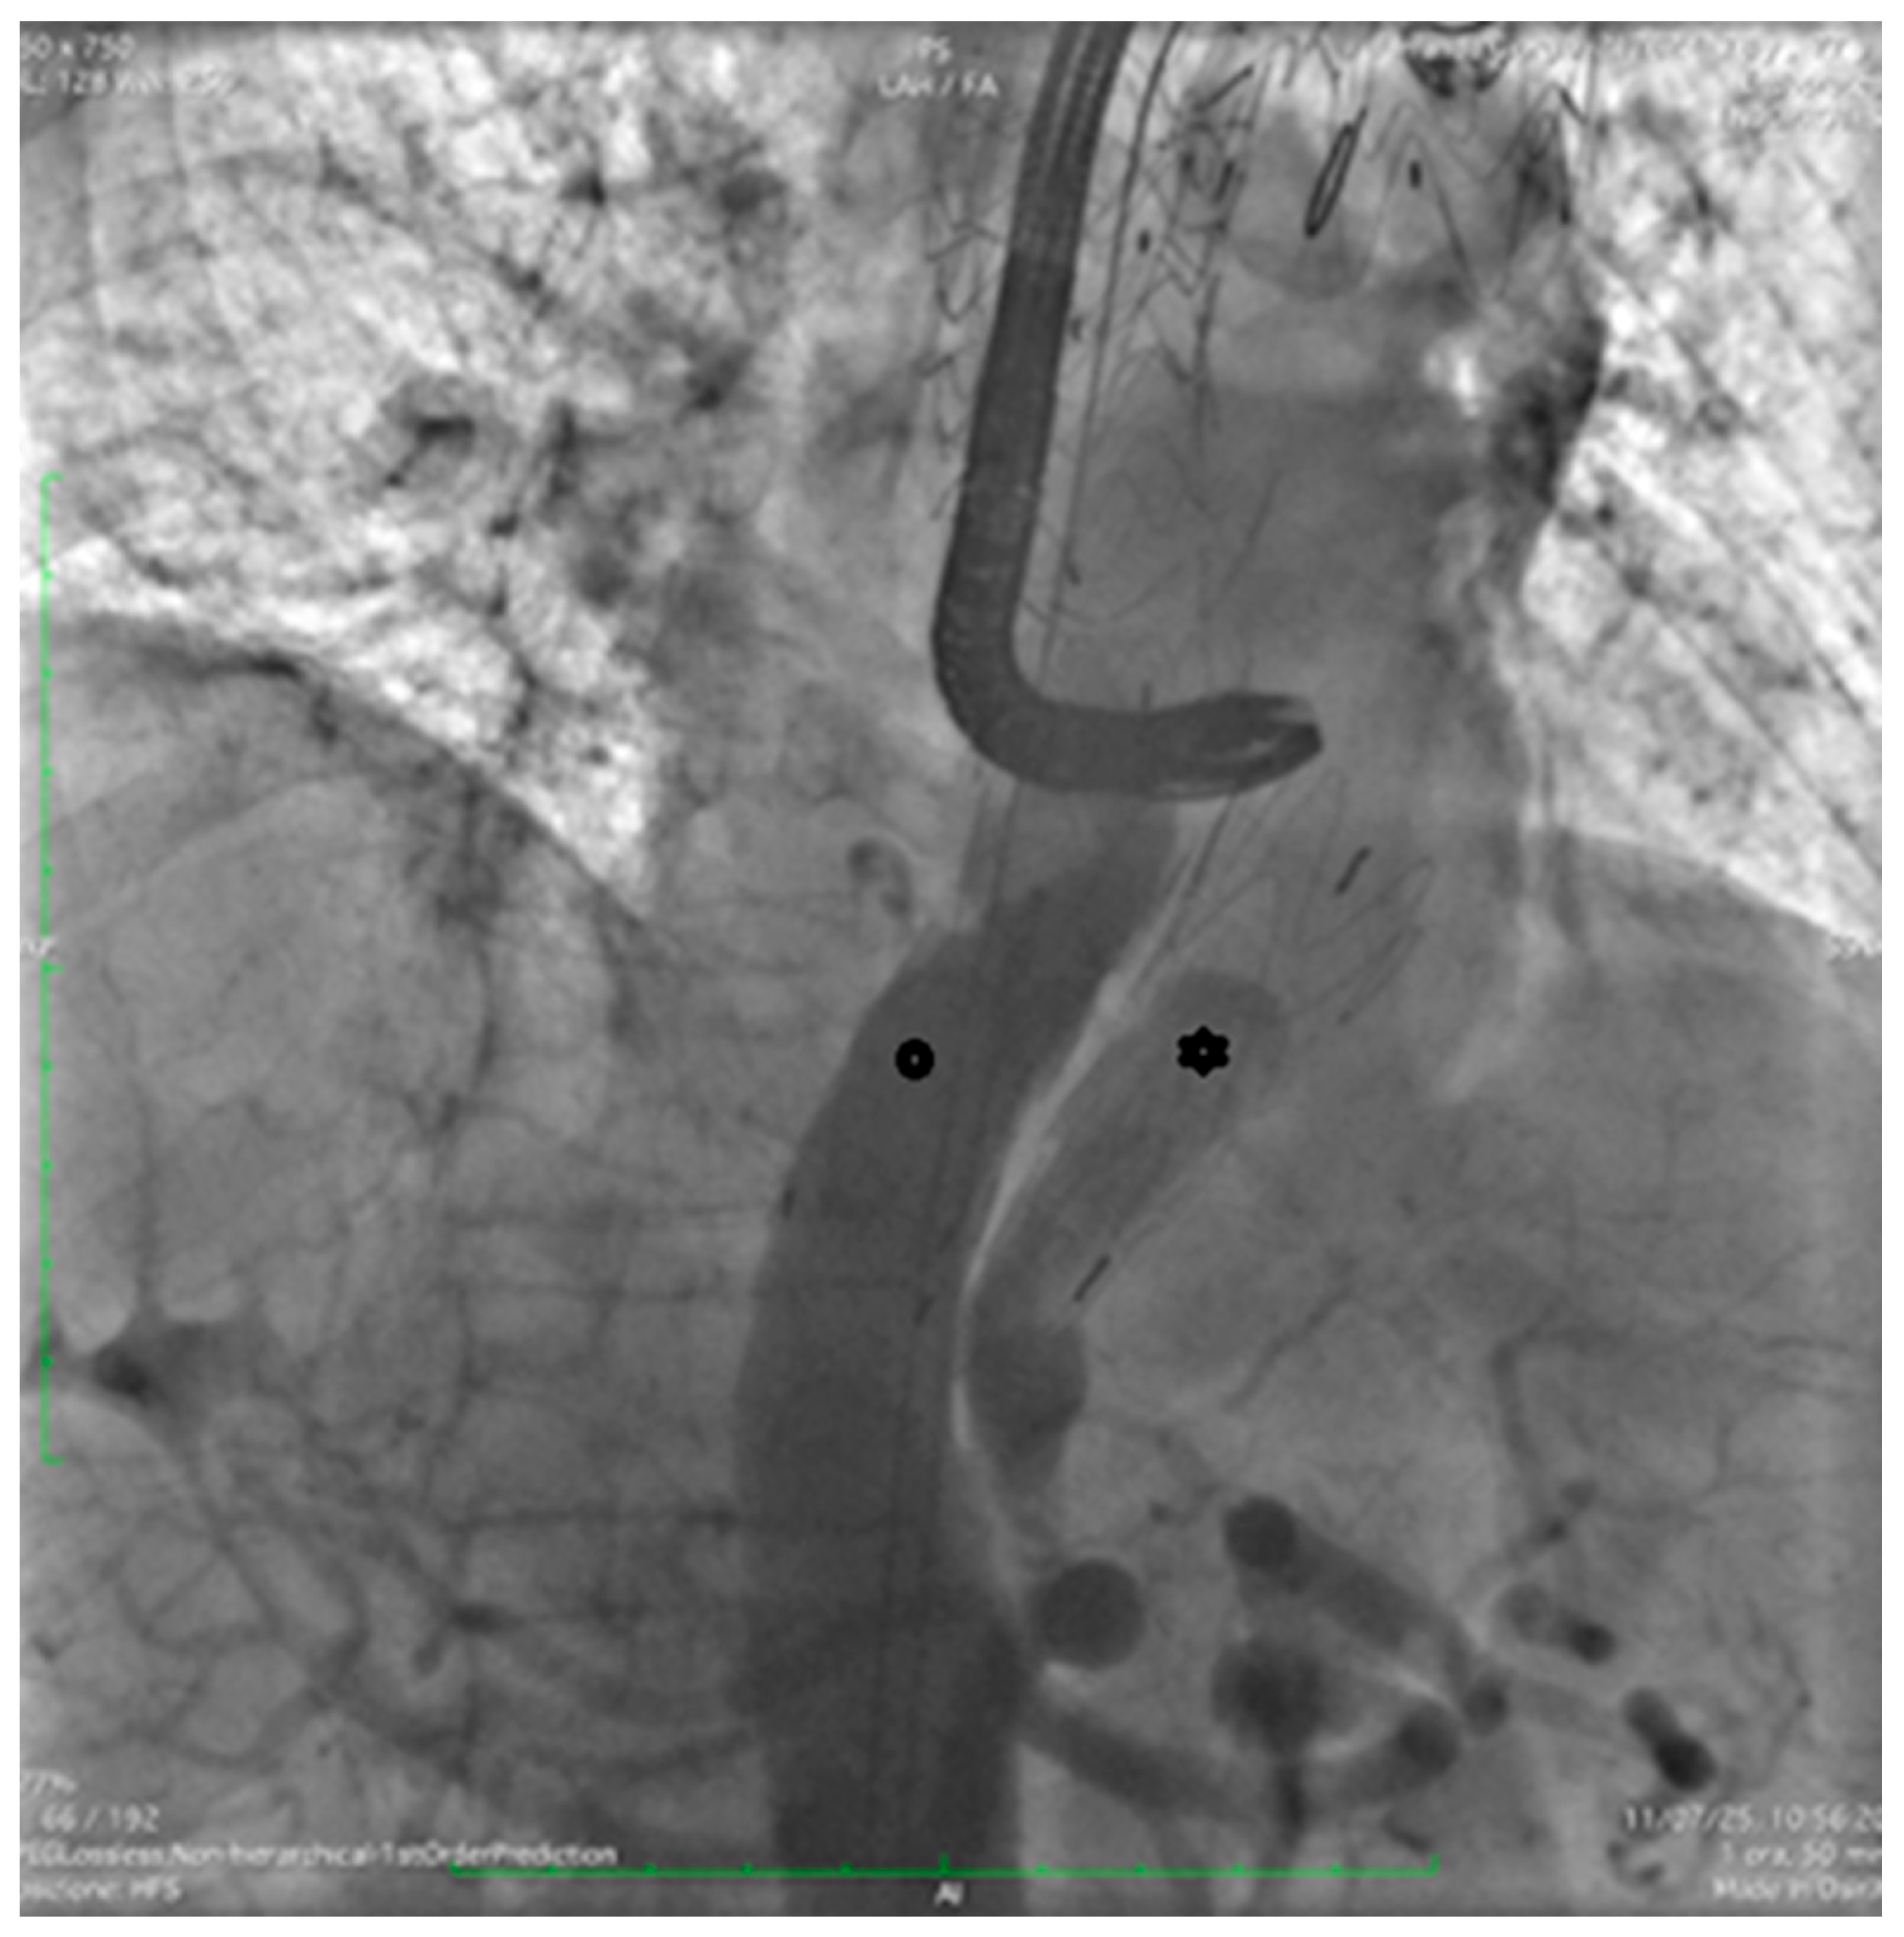

Follow-up computed tomography angiography (CTA) carried out in June 2025 revealed recanalization of the FL, extending from the distal aortic arch (zone 3) to the level of the superior mesenteric artery (zones 6–7). The descending thoracic aorta (DTA) demonstrated aneurysmal degeneration, with a maximum diameter of 58.5 mm (Figure 1).

Figure 1.

Computed tomography angiography (CTA) showing prior TEVAR (arrow) with recanalization of the false lumen (FL) through a proximal tear (*) near the stent graft and a distal tear (**) in zones 6–7.